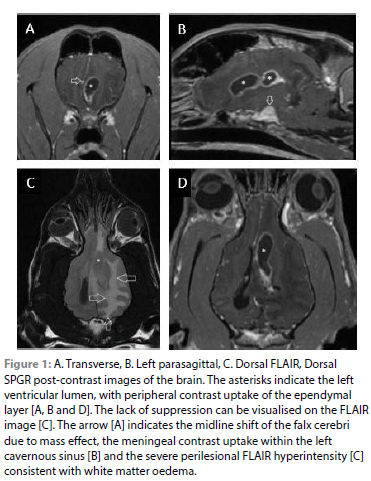

The dog was premedicated with butorphanol (0.2 mg/kg IV, Dolorex 10 mg/ml, MSD Animal Health) and diazepam (0.2 mg/ kg IV, Valium 10 mg/2 ml, Pharmaco Distribution LTD), induced with propofol (1 mg/kg IV per bolus, Propoven 1%, Fresenius Kabi, South Africa) to effect and placed in dorsal recumbency for MRI of the head using a 1.5 Tesla scanner (Optima™ MR450w, GE Medical Systems). The study consisted of T2-weighted images in the sagittal and transverse planes, T2* images in the transverse plane, pre- and post-contrast T1-weighted SPGR images in the transverse plane with reconstructions in the dorsal and sagittal planes, a FLAIR sequence in the dorsal plane, and dorsal plane DWI and ADC maps. Post-contrast imaging was performed immediately after injection (0.2 mmol/kg of 0.5 mmol/ml gadopentetate dimeglumine, Magnevist, Bayer LTD). All images were obtained at 3 mm slice thickness, except the SPGR images which were at 1.2 mm. There was severe ring-like ependymal contrast enhancement of the left ventricle, which contained non-enhancing T2-weighted hyperintense, T1 weighted hypointense but hyperintense to normal CSF, FLAIR non-suppressing material indicative of cellular or proteinaceous content. Some of the material in the middle of the ventricle was more rounded and T2W hypointense and T1W isointense, but non-enhancing. The rostral horn of the left ventricle was rounded, dilated and extended in a rostral direction, creating obvious ventricular asymmetry. This region was focally hyperintense on DWI and hypointense on the ADC map, consistent with restricted diffusion. There was asymmetrical plaque-like meningeal contrast uptake of the left cavernous sinus. A few small T1W, T2W and T2* weighted hypointense non-enhancing regions, were present within the cavernous sinus, most likely representing haemoglobin degradation products. There was severe white matter FLAIR hyperintensity surrounding the left lateral ventricle, affecting the entire left cerebral hemispheral corona radiata, consistent with perilesional oedema and resulting in severe mass effect, including compression and distortion of the left thalamus, mild subfalcine and infratentorial herniation, and marked midline shift to the right. There was mild segmental but extensive meningeal contrast uptake, affecting both lepto- and pachymeninges. The extracranial structures such as the caudal nasal passages, nasopharynx/nasopharyngeal meatus, orbits and ears were normal, without close proximity to the above pathology.

These findings indicated severe unilateral (left lateral) ventriculitis and meningitis, especially of the left cavernous sinus, and severe perilesional oedema resulting in marked mass effect. The most likely differential diagnosis for the lesion was infectious but with an origin not demonstrated (no otogenic spread, no cranial defect, no nasal spread/cribriform penetration noted). Non-infectious inflammatory disease, vascular disease, congenital causes, or neoplasia were considered inconsistent with the MRI changes.

Literature describing MRI findings of bacterial ventriculitis in dogs is sparse. Characteristic findings in humans include ventricular debris, ependymal contrast enhancement, periventricular signal abnormalities and signs of meningitis (Fukui et al. 2001). In this dog, the most prominent findings were ependymal contrast enhancement, ventricular debris and periventricular signal abnormalities, which is similar to MRI findings in a dog diagnosed with cerebral ventriculitis associated with otogenic meningoencephalitis (Wu & Chang 2015). These characteristic MRI findings may prove useful in making a provisional diagnosis of ventriculitis, allowing earlier initiating of treatment pending CSF analysis.